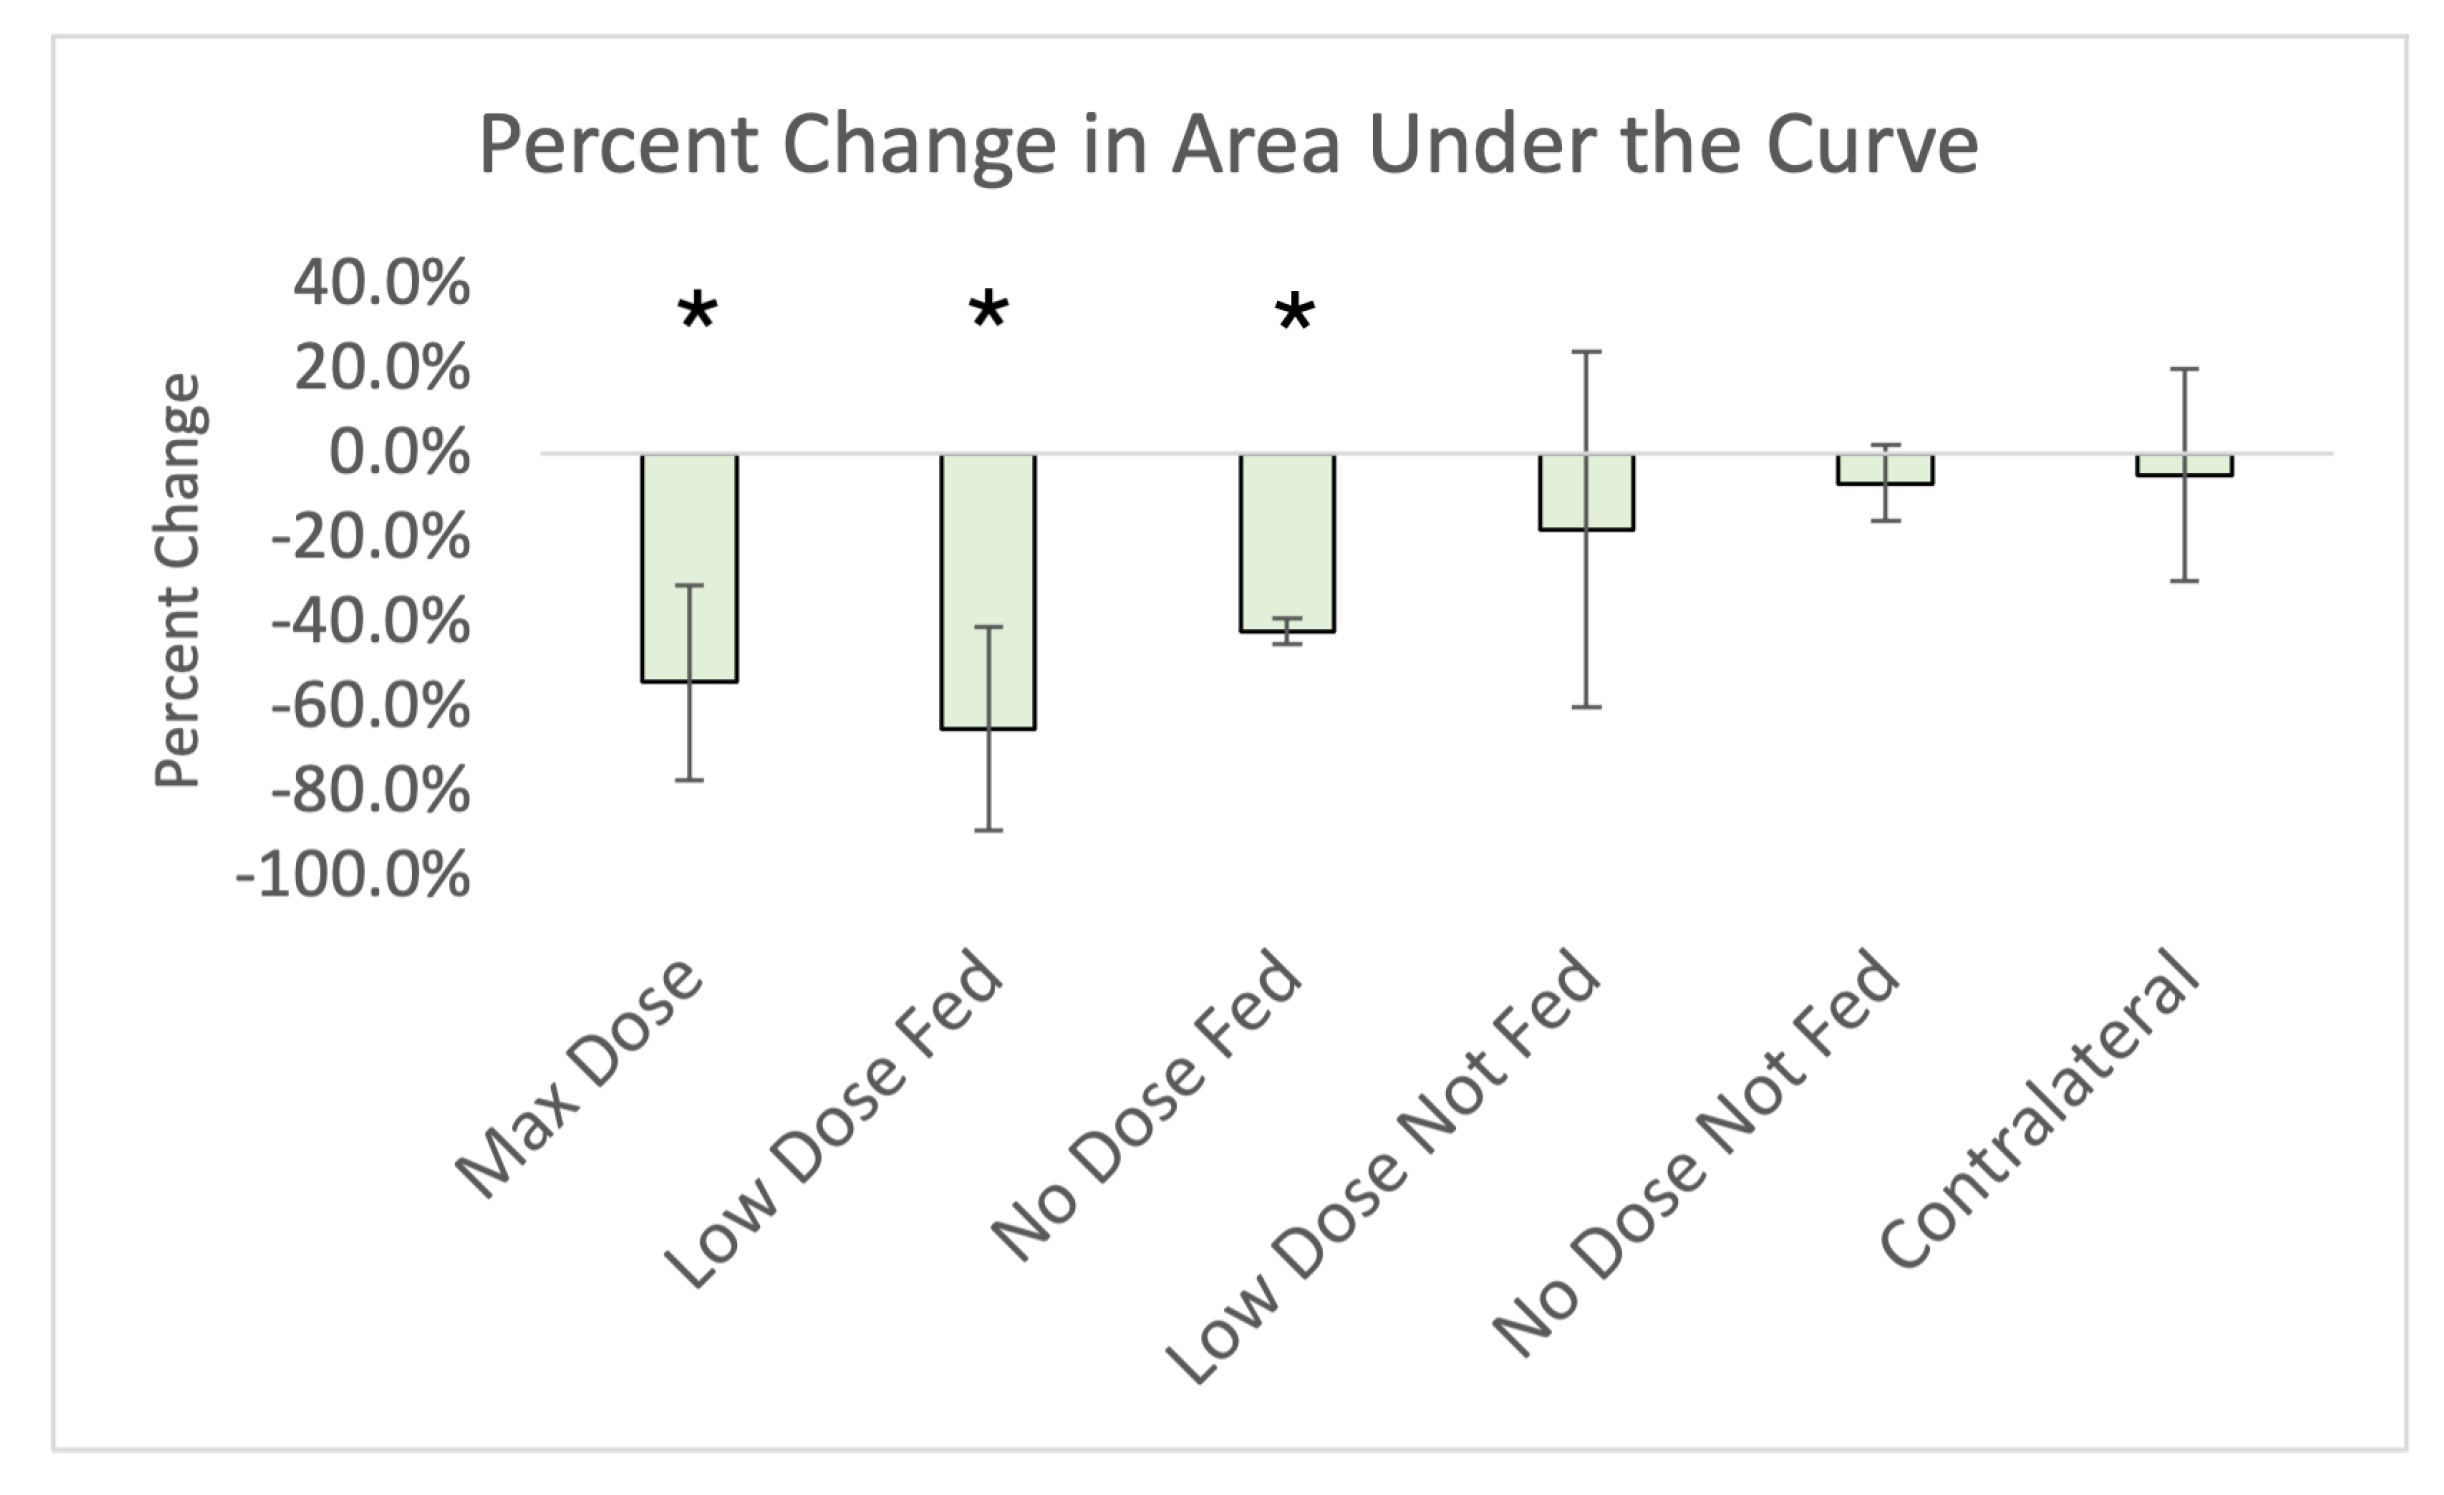

2.5.2. Area under the Curve

3. Results

Imaging Results

4.1. Changes in Kinetics

4.1.1. Ipsilateral Contours

4.1.2. Contralateral Lung

| Max Rise | Max Value | Baseline to Baseline Time | Baseline to Baseline Difference | Slope Up | Slope Down | Area under Curve | |

|---|---|---|---|---|---|---|---|

| Max Dose (Ipsilateral) | −40.7% (16.1%) * | −41.7% (18.1%) * | −26.3% (16.8%) * | −68.5% (23.1%) * | −43.0% (16.3%) * | −47.1% (19.2%) * | −56.0% (21.0%) * |

| Low-Dose Fed (Ipsilateral) | −42.6% (33.4%) * | 13.6% (201.6%) | −3.9% (32.9%) | −125.0% (99.1%) | −47.7% (34.0%) * | −66.4% (25.9%) * | −65.0% (24.0%) * |

| No-Dose Fed (Ipsilateral) | −28.4% (47.8%) | −128.1% (232.6%) | −20.8% (32.0%) | −32.7% (9.7%) * | −50.6% (33.3%) * | −36.7% (42.4%) * | −55.0% (27.0%) * |

| Low-Dose Not-Fed (Ipsilateral) | −24.3% (52.6%) | −14.9% (68.8%) | −9.7% (43.9%) | −46.9% (41.0%) | 80.3% (212.4%) | −38.6% (41.4%) | −36.0% (54.0%) |

| No-Dose Not-Fed (Ipsilateral) | −32.0% (32.0%) | −29.4% (35.3%) | 3.1% (38.4%) | −47.7% (18.0%) * | 79.9% (160.1%) | −1.3% (91.8%) | −24.0% (23%) |

| Contralateral | 5.8% (15.2 %) | 2.0% (12.1%) | −3.2% (33.2%) | −3.1% (5.0%) | 40.5% (114.9%) | 17.9% (40.1%) | −5.0% (25.0%) |